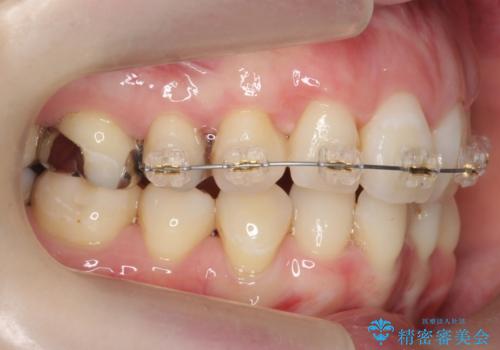

上にはワイヤー部分矯正を行った後、インビザラインでマウスピース矯正を行っています。

今回は特に左上の犬歯は歯肉退縮して根が露出していたのもあり、抜歯をお勧めしました。